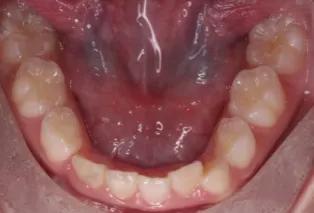

Photos intra-orales